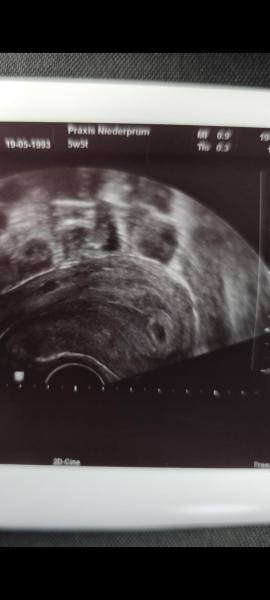

Hallöchen 🙋🏼‍♀️  Was sagt ihr zu meinem Ultraschallbild?  Bin nervös und freu mich auf die Zukunft...⏳ ET im August 🥰 LG          Smiley nr215.gif

Ich sehe ganz klar eine Schwangerschaft. Hat der Arzt denn mehrere gesehen? Wie weit bist du denn und wann ist dein ET? Das Ultraschall Bild find ich irgendwie seltsam, da ma nicht wirklich was erkennt. Müsste man da jetzt nicht den dottersacksehen und Embryo?

Naja, der Ultraschall wurde Vaginal gemacht, das ist wohl erwähnenswert, sorry...  🫣 Ich sehe da selbst irgendwie 2 Mini-Fruchtblasen links und rechts 🤷🏼‍♀️ Morgen ist der 1.Vorsorge-Termin und ich bin Ende der 9.ssw 🤰🏼 Mein Bauch wächst auch schon...🥰   LG, danke & alles Gute euch 🍀

Huhu :-) Wie kommst du auf Zwillinge? Was hat der Arzt/Ärztin gesagt? Ich sehe nur eine Fruchthöhle. Der Rest oben scheint der Darm bzw ist nicht die Gebärmutter.  Wie weit bist du? Bald kann man dann schon mehr sehen ☺️   Und herzlichen Glückwunsch!